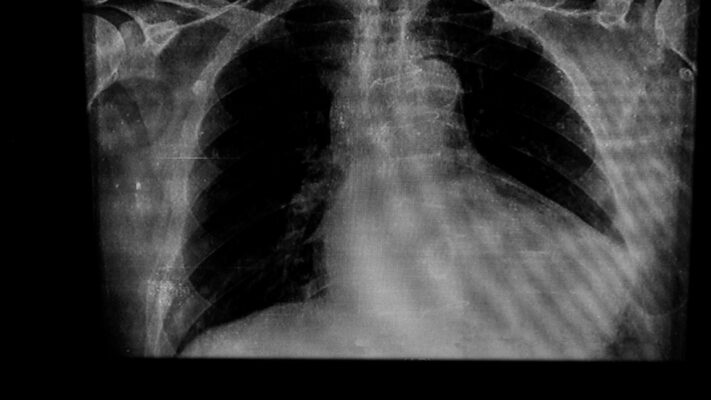

Her Göğüs Ağrısı Kalple İlgili midir?

Her göğüs ağrısı kalp kaynaklı değildir; kas-iskelet sistemi, mide-bağırsak sistemi, akciğerler ve psikolojik faktörler gibi [...]